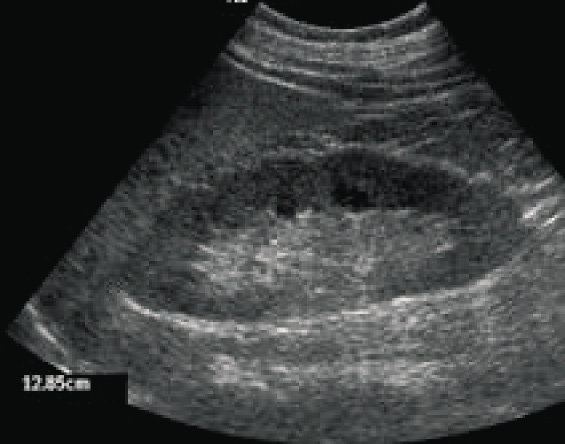

Al momento della visita presso la nostra struttura la paziente pesa 84 kg, con Body Mass Index (BMI) di 30,9 kg/m2 e una circonferenza vita di 93 cm. All’esame obiettivo (EO) la pressione arteriosa (PA) risulta di 145/95 mmHg, la frequenza cardiaca 68 bpm ritmica, con presenza di lievi edemi declivi agli arti inferiori. L’obiettività cardiaca, toracica e addominale è nei limiti di norma. La paziente porta in visione esami ematochimici (Tabella I) che evidenziano danno renale con proteinuria, scarso controllo glicemico e ipercolesterolemia (LDL 183 mg/dl). L’ECG effettuato poco tempo prima non mostra anomalie riconducibili a ipertrofia ventricolare sinistra, disturbi del ritmo o della conduzione né segni di ischemia miocardica (Figura 1). L’ecografia renale evidenzia reni di dimensioni normali, diametro longitudinale 12 cm bilateralmente, con corticale di normale spessore ma lievemente iperecogena (Figura 2). Al momento della visita la paziente assume terapia con ACE-inibitore, calcio antagonista, antiaggregante, statina e associazione di metformina e sulfanilurea. Inoltre, riferisce saltuario uso di FANS per osteoartrosi (Tabella II).

Figura 2. Ecografia renale: reni di normali dimensioni (diametro longitudinale di 12,5 cm), corticale con spessore conservato, ma iperecogena